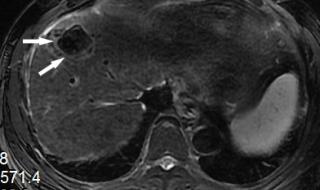

原发性肝癌,又叫肝癌,是肝脏细胞或肝内胆管上皮细胞发现的恶性肿瘤。肝脏发现肿瘤,可以是肝脏本身产生的,也可以是其他部位转移而来的。如果比如胃癌转移到肝脏,叫胃癌肝转移。原发性肝癌在我们最常见的是慢性肝炎导致肝硬化,发展成原发性肝癌。

原发性肝癌